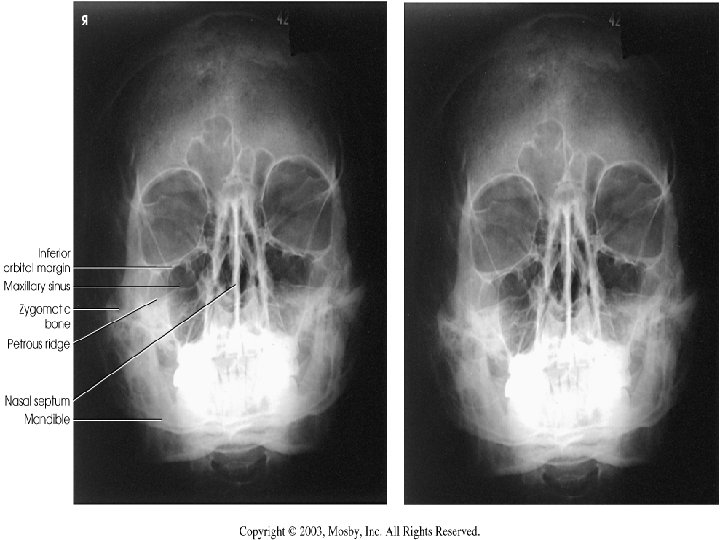

Modified Waters Radiograph n Petrous ridges projected immediately below the inferior border of the orbits n Equal distance from lateral orbit to lateral skull on both sides

PA Axial- Caldwell Radiograph n Equal distance from lat skull to lat orbit n Symmetric petrous ridges in lower 1/3 orbit n Penetration of frontal bone without excessive density at lateral borders of skull.